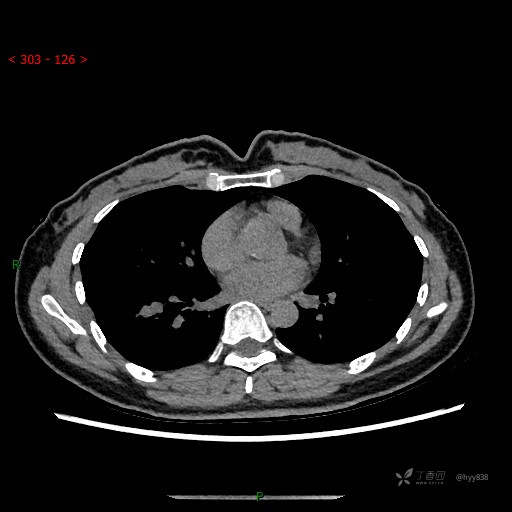

胸部CT平扫